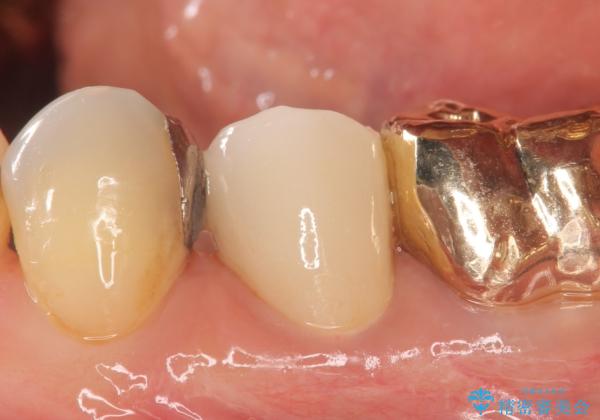

オールセラミッククラウン 再根管治療後の補綴

- 左下5番目の歯を根管治療からやり直したいといらっしゃった方の症例です。

再根管治療終了後、オールセラミッククラウンによる補綴を行いました。

今回用いたオールセラミッククラウンはジルコニアフレームという白い素材の上にセラミックを盛っているため、審美性が非常に高いのが特徴です。

また、ジルコニアは人工ダイヤモンドの材料にも使われているほど高い強度を持っており、そのためオールセラミッククラウンは審美性だけでなく、奥歯やブリッジの補綴も可能とするクラウンです。